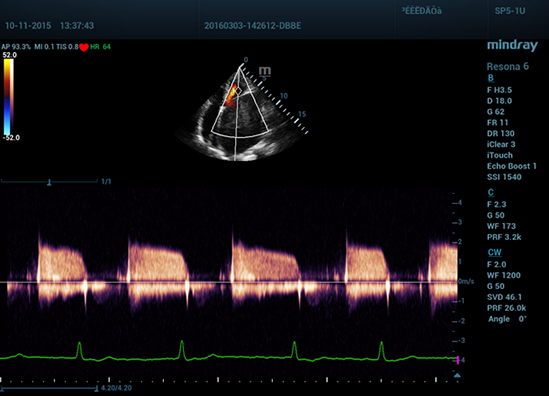

• 11 Mitral Stenosis

Стеноз митрального клапана